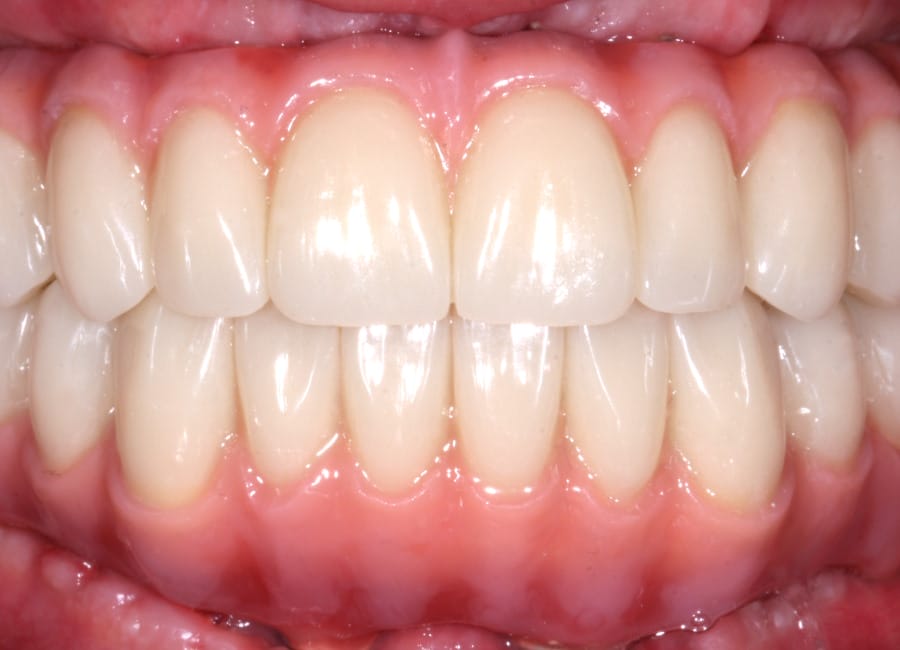

The moment Natalie saw her new smile, the emotion was undeniable. What had once been a source of discomfort, anxiety, and embarrassment had been completely transformed. Her new teeth restored full function and aesthetics, giving her back the ability to eat, speak, and smile without hesitation.

This result was more than cosmetic. It marked the end of a long journey filled with fear and hesitation, and the beginning of a new chapter defined by confidence and well-being. Natalie’s story is a powerful example of how modern dentistry, when led by skilled professionals and supported by cutting-edge technology, can restore much more than teeth.

My first look in the mirror with my new set of teeth was incredible. I’m in disbelief and I feel a bit overwhelmed because it looks so good. At the same time, it looks so natural, it is the shape of my natural teeth and smile. They feel comfortable, I can speak with them. I feel very confident that this will work very well for me.